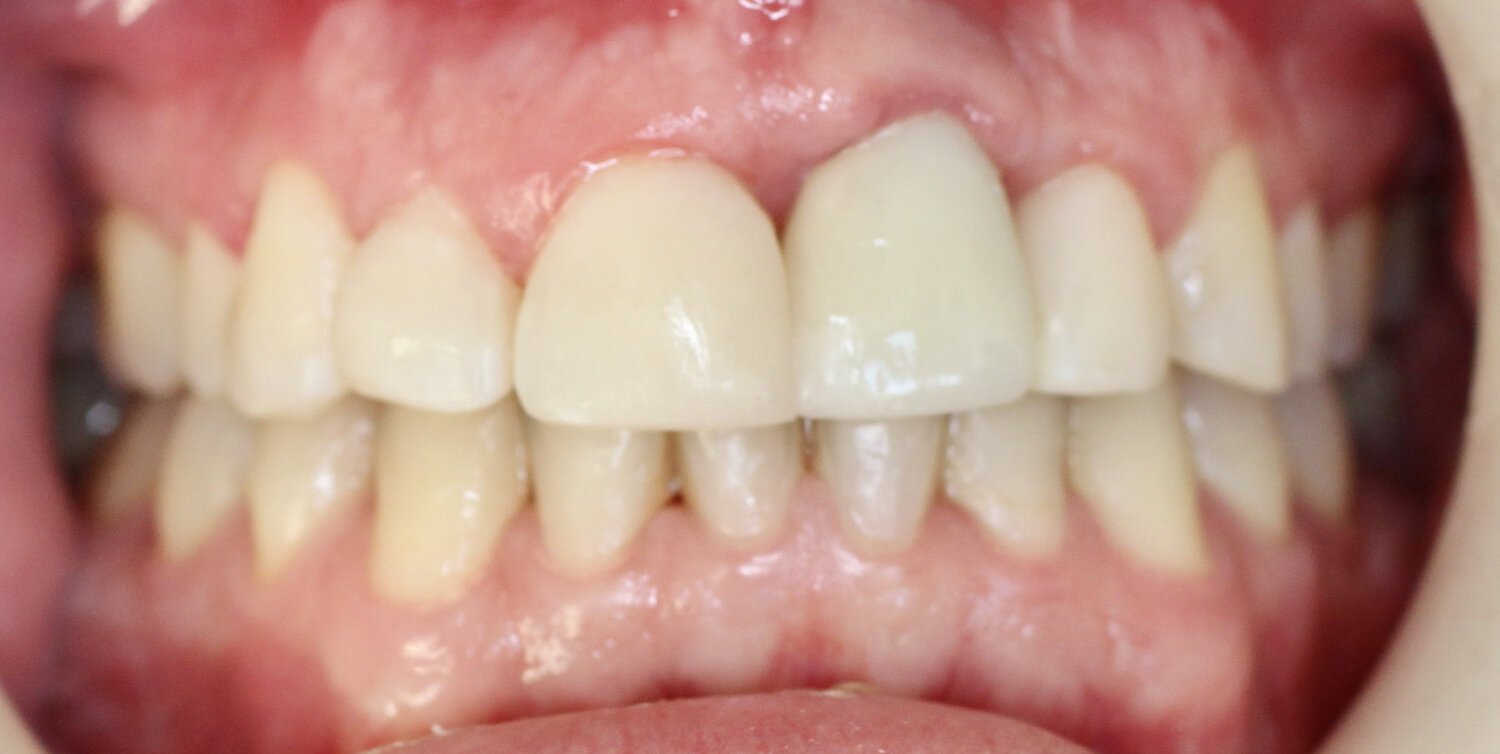

BEFORE

AFTER